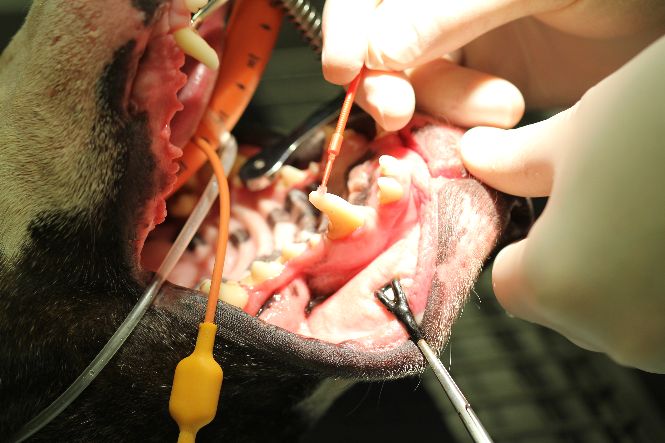

Tooth preparation for cementation

Coating inside of crown with cement ready for cementation

Fitting of crown to tooth